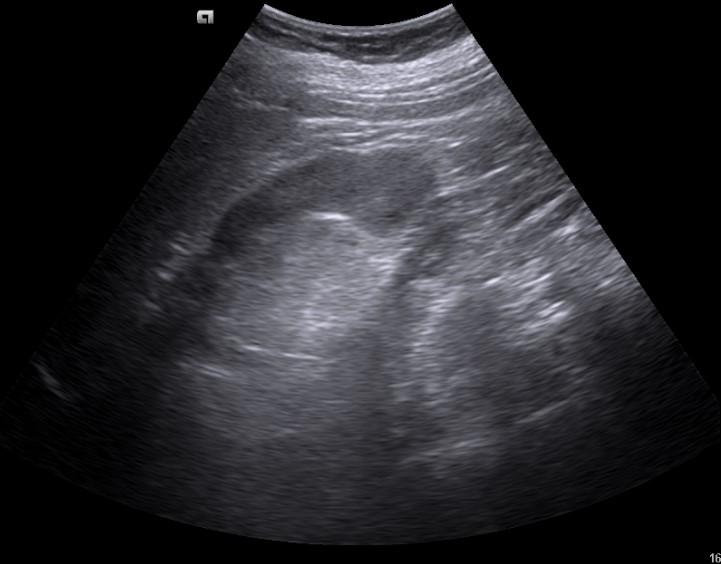

Case of the Week 32 2016 *58-year-old female. What is the most likely diagnosis? Answer: Renal angiomyolipoma Kategori:Cases Önceki yazı Case of the Week 30 2016 Sonraki yazı Case of the Week 5